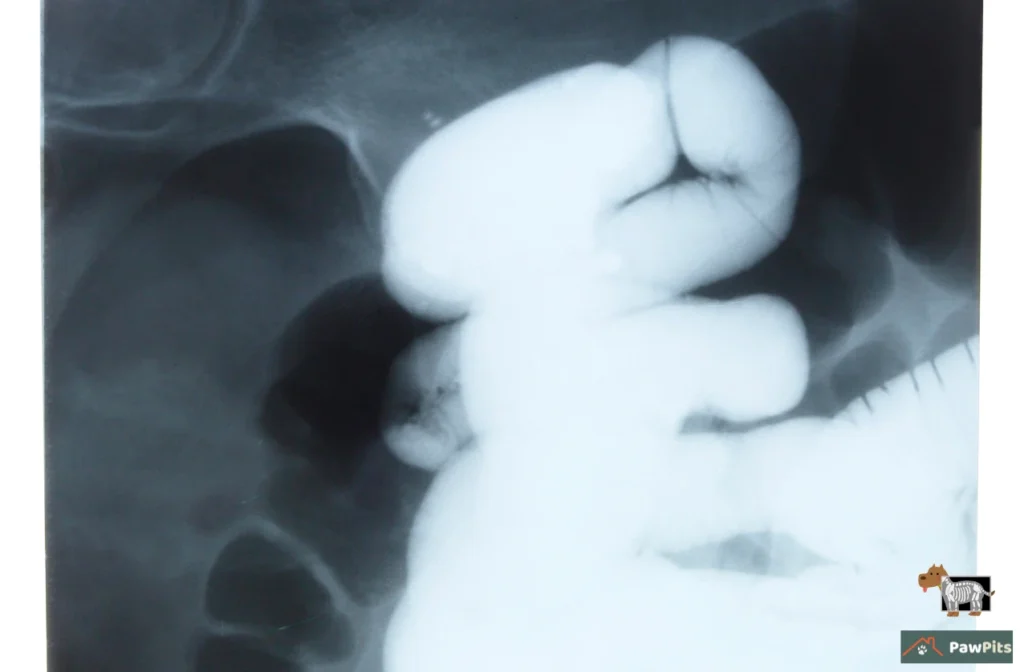

Pictures Don’t Lie (Mostly)

That’s when the X-rays or ultrasound come in. And let me tell you, waiting for those results feels like hours even if it’s ten minutes. On the screen, you’ll see shapes and shadows, sometimes clear (yep, that’s a sock), sometimes just gas bubbles that scream “blockage.” Bloodwork usually follows, not to find the object, but to check if dehydration or infection’s already setting in.